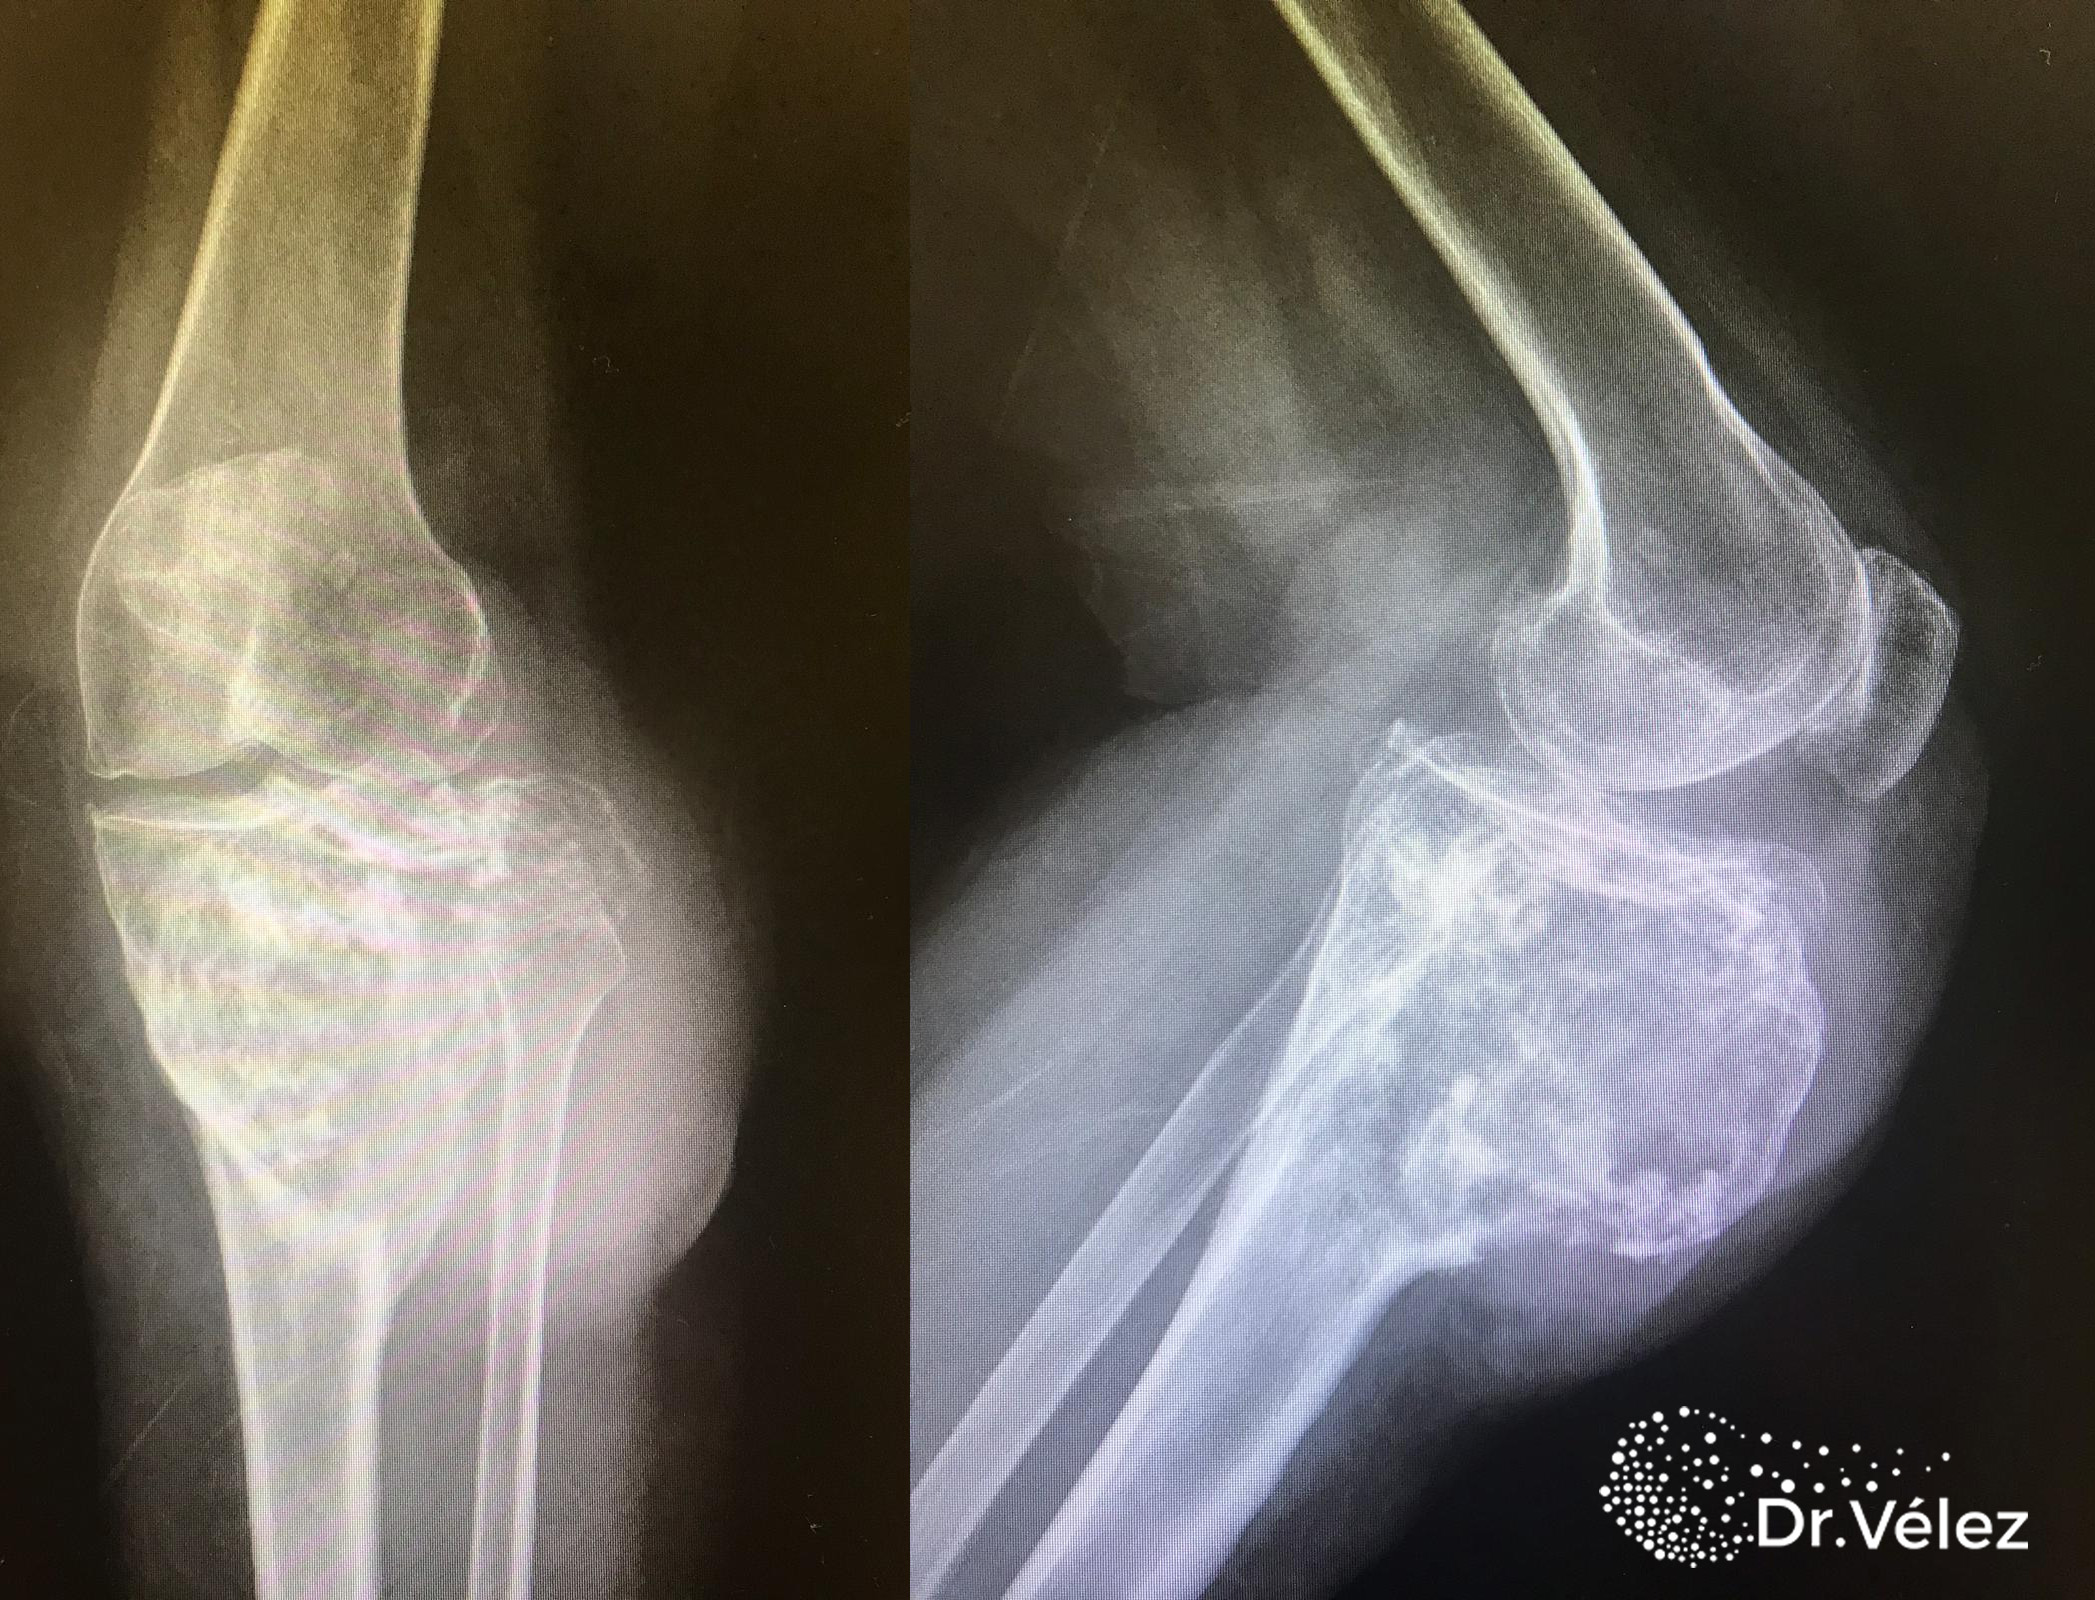

Остеосаркома коленного сустава: информация и поддержка

Раздел: Необычные решения